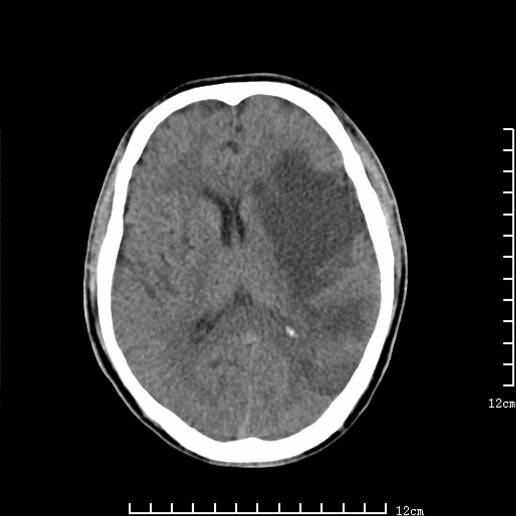

以下图像分别是3月25日凌晨及下午图像、3月27日、4月16日的ct图像。

3月25日凌晨